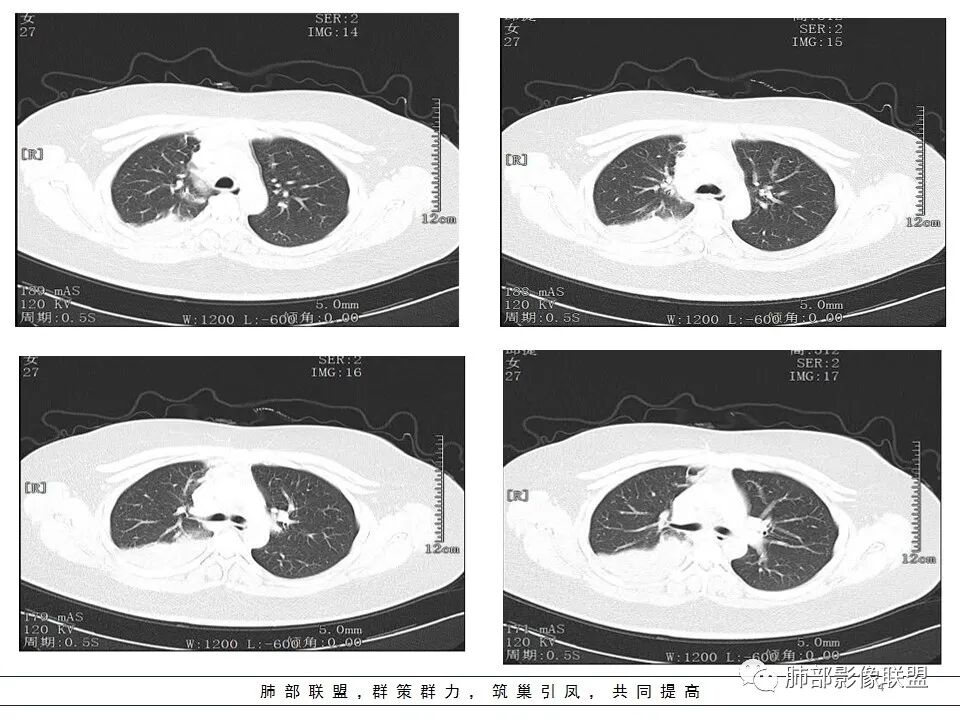

右肺体积缩小,右肺门可见片状影,叶支气管堵塞,呈低密度,无强化,其内似可见点状高密度钙化,病变外周膨隆,右肺下叶大片状致密影,增强后明显强化,其内血管走形自然,右肺下叶呈肺不张改变。纵隔肺门无肿大淋巴结。年轻女性,高热、黄痰来诊。综合考虑:右肺中、下叶综合征合并下叶肺不张,考虑炎性病变,炎性叶支气管阻塞可能性大,早期肺脓肿?结核有点不符合,无胸水,病灶形态太单一。

右肺中叶粘液栓,中叶低密度肿块,密度均匀,延迟强化,右肺下叶不张,考虑炎性病变

临床发热,腹泻,咳黄痰,应该是感染性病变。影像表现为下叶,中叶支气管堵塞,远端支气管内粘液潴留,所属肺组织不张,膈肌明显升高,上叶代偿性肺气肿,增强似乎可见中间段支气管处一个强化结节,考虑中间段支气管占位性病变合并远端支气管粘液潴留,感染可能,肿瘤性质不好定,太年轻,猜一个,粘液表皮样癌

患者青年女性,发热6 天,咳嗽、咳痰3天。为黄脓痰。胸部CT:右肺体积稍小,右中间支气管肿物堵塞,中叶、下叶大片实变不张,与正常肺组织分界清楚。增强实变影明显强化,右下肺支气管近心端见类圆形强化结节影,血管纤细,部分支气管显影变细,纵隔淋巴结肿大。结合无呼吸困难症状,病程长。综合考虑低度恶性病变并阻塞性肺炎,类癌可能大,鉴别结核、淋巴瘤。

第一个问题:定位

下叶?还是多叶?

因为这个很关键

例如:上叶、下叶、中叶都受累;中、下叶病变;下叶病变不一样。

上、中、下都有,我要看主支气管,如果主支气管没问题,我不考虑阻塞的问题

中下叶有——中间段支气管

下叶——下叶支气管

我们捋一捋病灶的范围

这是上叶血管

我再捋一捋支气管

右主支气管

上叶支气管

中间段

争议的地方这是上叶?中叶?

说实话图不全

关键点——中间段支气管堵塞处

没有显示

都是以肺内的病变为主

其实关键点在中间段支气管

本病例特点是中叶病灶和下叶病灶不一样,支气管腔内的病灶又是怎么样的呢?我们要是有沿支气管重建的冠状位、矢状位会更有利于分析。第一,中叶病灶明显粘液样改变、低密度,且低密度区有占位效应、膨隆,确实要考虑粘液表皮样癌。第二,中叶和下叶支气管显示不出来,但血管显示出来了。中叶病灶血管稀疏、细小,下叶病灶血管粗大、走形正常。朝外肺不张实变,不是单纯的肺不张,肺不张一般体积明显缩小、血管聚拢,该病例肿瘤于其中成分不一样,所以上叶部分病灶考虑为下叶病灶占位效应及膈面向上推压引起,中叶萎缩。综合腔内堵塞、纵隔淋巴结肿大要考虑恶性。